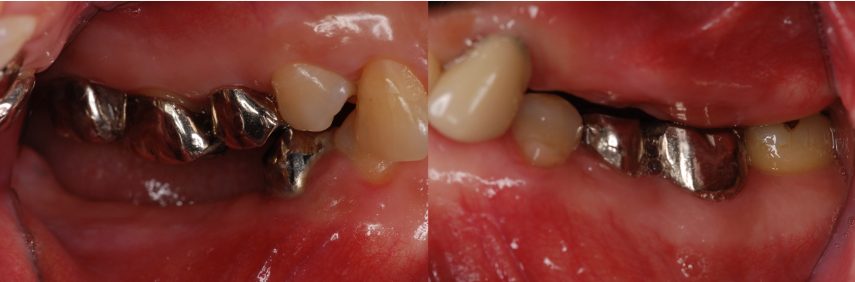

| 主訴 | 全顎治療希望、全顎的に歯が動く、奥の歯がなくて噛めない。できるだけ綺麗で噛めるようになりたい。 |

| 治療内容 | 全顎的に歯周病、前歯部の被蓋が深く、重度歯列不正が認められるため、 歯周外科を含む歯周治療、矯正治療、インプラント治療、セラミックによる補綴治療後メインテナンスに移行しました。 |

| 想定されたリスク | 矯正治療の後戻り、歯周病の再発、食いしばり(パラファンクション)によるセラミックの破折、歯の破折のリスクがありました。 |